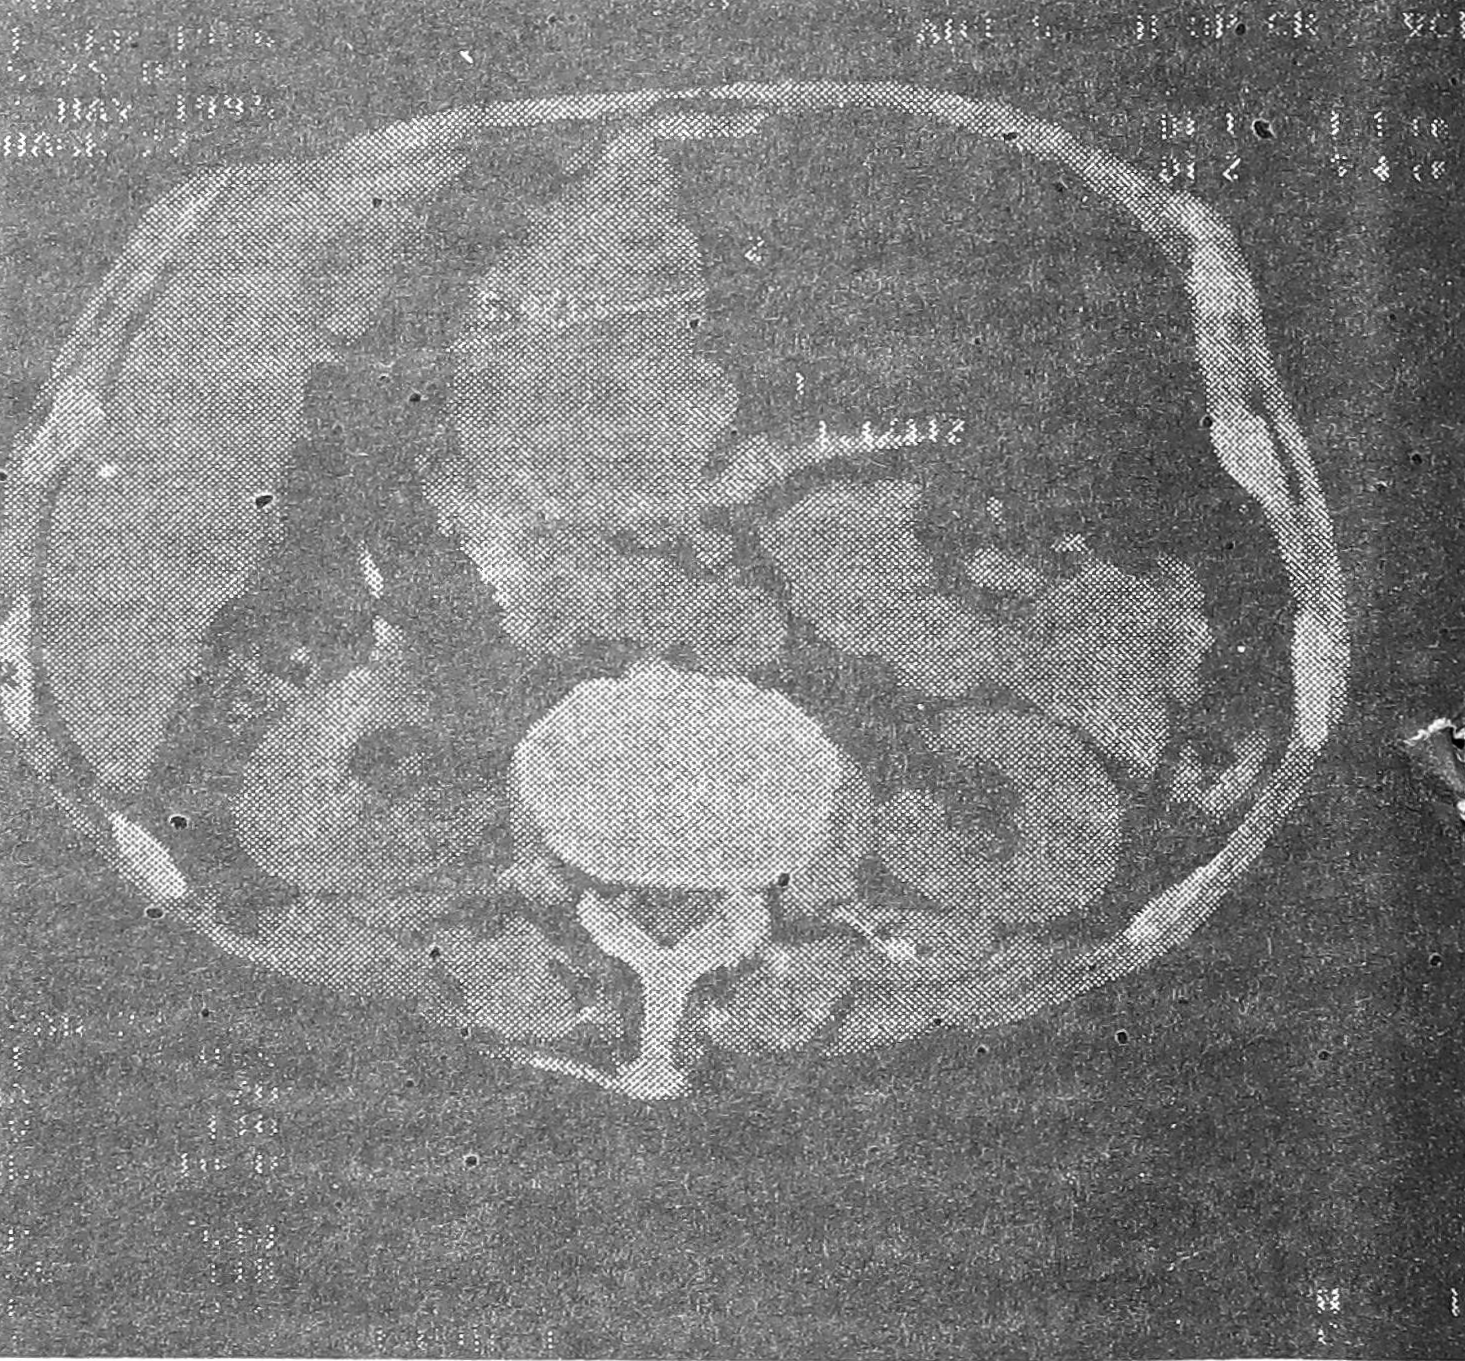

Результаты компьютерно-томографических исследований у больных, страдающих эндофитными формами рака желудка, показали, что толщина стенки желудка в пораженном опухолью месте составила более 1 см (в то время как в нормальных условиях — 0,2—0,4 см). Наряду с утолщением стенки желудка в месте поражения наблюдались и другие признаки (особенно в случае выявления запущенных карцином): неровность, бугристость контуров утолщения, нарушение эластичности стенки желудка в месте поражения, прорастание в соседние анатомические структуры (рис. 1— 3). Таким образом, в диагностике эндофитного рака желудка РКТ является дополнительным методом исследование несущим в большинстве случаев ценную специфическую информацию о характере неопластического процесса в стенке желудка. Ее следует более широко использовать в клинической практике после традиционного рентгенологического и эндоскопического методов. Если традиционной рентгенографии желудка выявляются признаки запущенного опухолевого процесса, то следующим этапом в обследовании такого больного методически рационально использовать РКТ (минуя этап эндоскопического исследования) с целью уточнения распространенности, перспективности дальнейшего оперативного лечения, установления регионарных и отдаленных метастазов.

Рис. 1. Больной П., 69 лет. Эндофитный рак малой кривизны тела желудка с прорастанием в соседние анатомические структуры. Размер утолщения (отмечен на снимке) достигает 5,4 см.